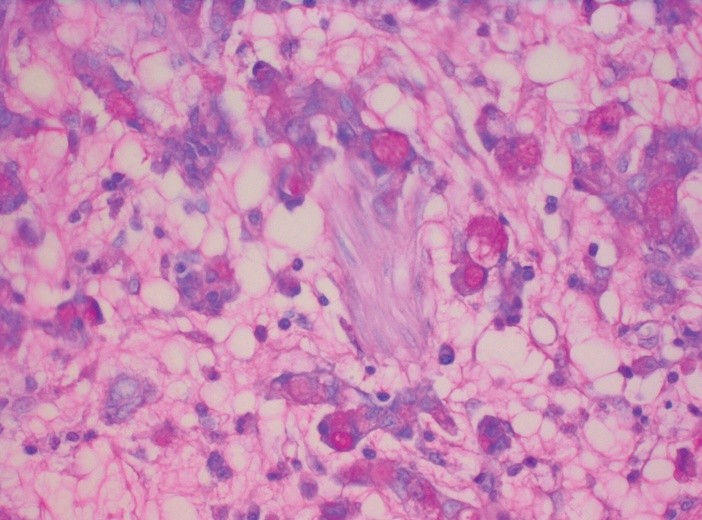

Taka hipoteza rozważana była już od kilku lat. Podejrzewano, że w guzie jest niewielka grupa komórek macierzystych (CSC - cancer stem cel), która potrafi się oprzeć zastosowanemu leczeniu, nawet jeśli różnymi metodami uda się zmniejszyć jego rozmiary. Z tych komórek po pewnym czasie u wielu chorych nowotwór znowu się powiększa i choroba nawraca.

Dotychczas nie było jednak na to dowodów. Dopiero trzy grupy badaczy po raz pierwszy wykazały, że taki jest mechanizm rozwoju choroby nowotworowej w przypadku guza mózgu, gruczolaków oraz raka skóry. "Udowodniliśmy to w co wielu specjalistów powątpiewało" - powiedział jeden z autorów badań prof. Luis Parada z University of Texas.

Amerykański uczony zidentyfikował nowotworowe komórki macierzyste w glejaku wielopostaciowym u myszy, najczęstszym złośliwym nowotworze mózgu. Prof. Cedric Blanpain z Wolnego Uniwersytetu w Brukseli wykrył je w raku kolczystokomórkowym skóry wywodzącym się z komórek naskórka. Z kolei badacze holenderscy z uniwersytetu w Utrechcie znaleźli je w gruczolaku, nowotworze przewodu pokarmowego, np. jelita grubego. Jego badania maja tę dodatkową wartość, że znalazł w nich mutacje Lgr5.

Z tych wszystkich badań wynika, że nowotworowe komórki macierzyste są podobne do zdrowych komórek macierzystych, z których regenerują się tkanki i narządy w całym organizmie. Różnią się jedynie tym, że nie przestają się dzielić, co jest charakterystyczne dla komórek rakowych. Potrafią też długo pozostawać w uśpieniu, by dać znać o sobie nawet po długim czasie.